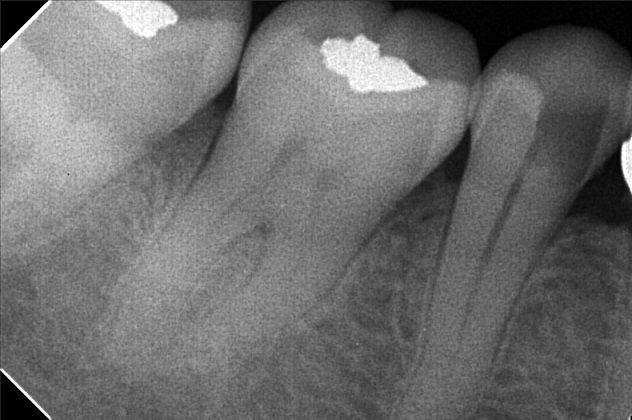

- Procedure

- File 2

- sevilla_02.jpg